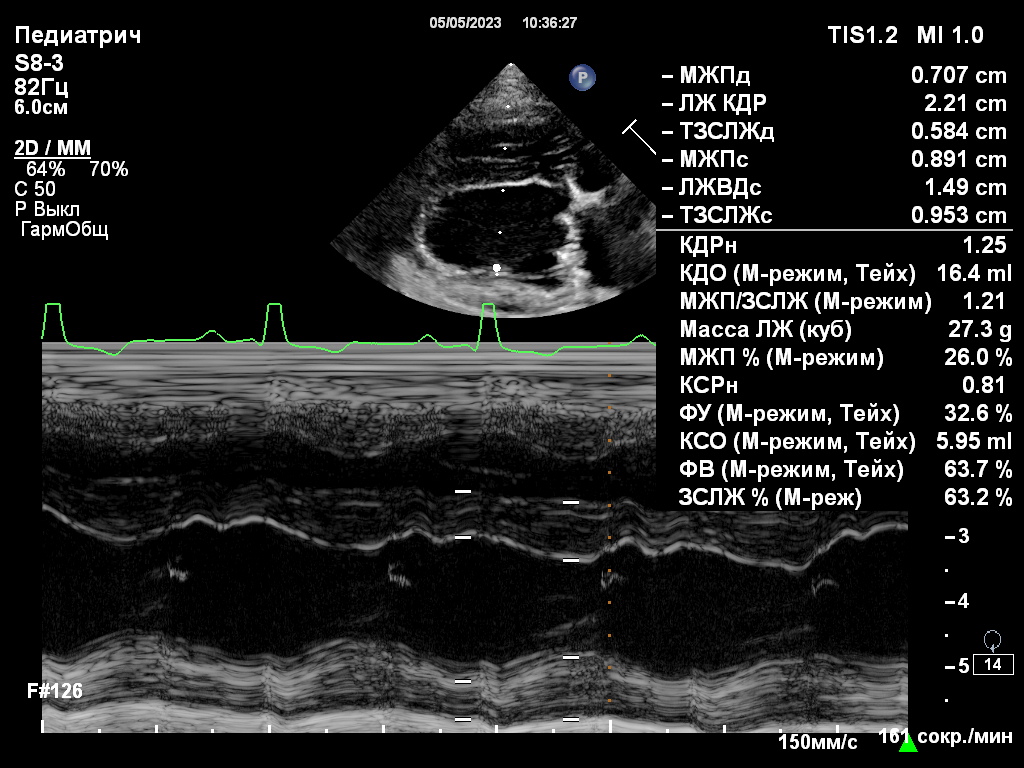

Фото 5-7. Двухмерная эхокардиография, правая парастернальная проекция, короткая ось, срез на уровне створок митрального клапана: значительное улучшение коаптации створок митрального клапана, регургитационные потоки формируются по краям от зоны их стягивания (фото 5); створки клапана стянуты край-в-край в сегменте А2, что обеспечивает основную пропускную способность клапана через зоны А1–Р1 и А3–Р3 (фото 6). Выраженное обратное ремоделирование миокарда левого желудочка (фото 7): уменьшение конечно-диастолического нормализованного размера ЛЖ до 1,3 (до операции КДРн – 1,9).

Пациент успешно стабилизировался в послеоперационном периоде.В течение первых дней наблюдалась умеренная апатия, однако аппетит был сохранен, что является положительным признаком восстановления. Эхокардиография, проведенная после операции, выявила значительное снижение степени митральной регургитации и уменьшение давления в левом предсердии с 19/13 мм рт. ст. до 11/4 мм рт. ст., что свидетельствует об успешной коррекции дефекта клапана и об эффективности проведенного хирургического вмешательства2 (фото 5-7).